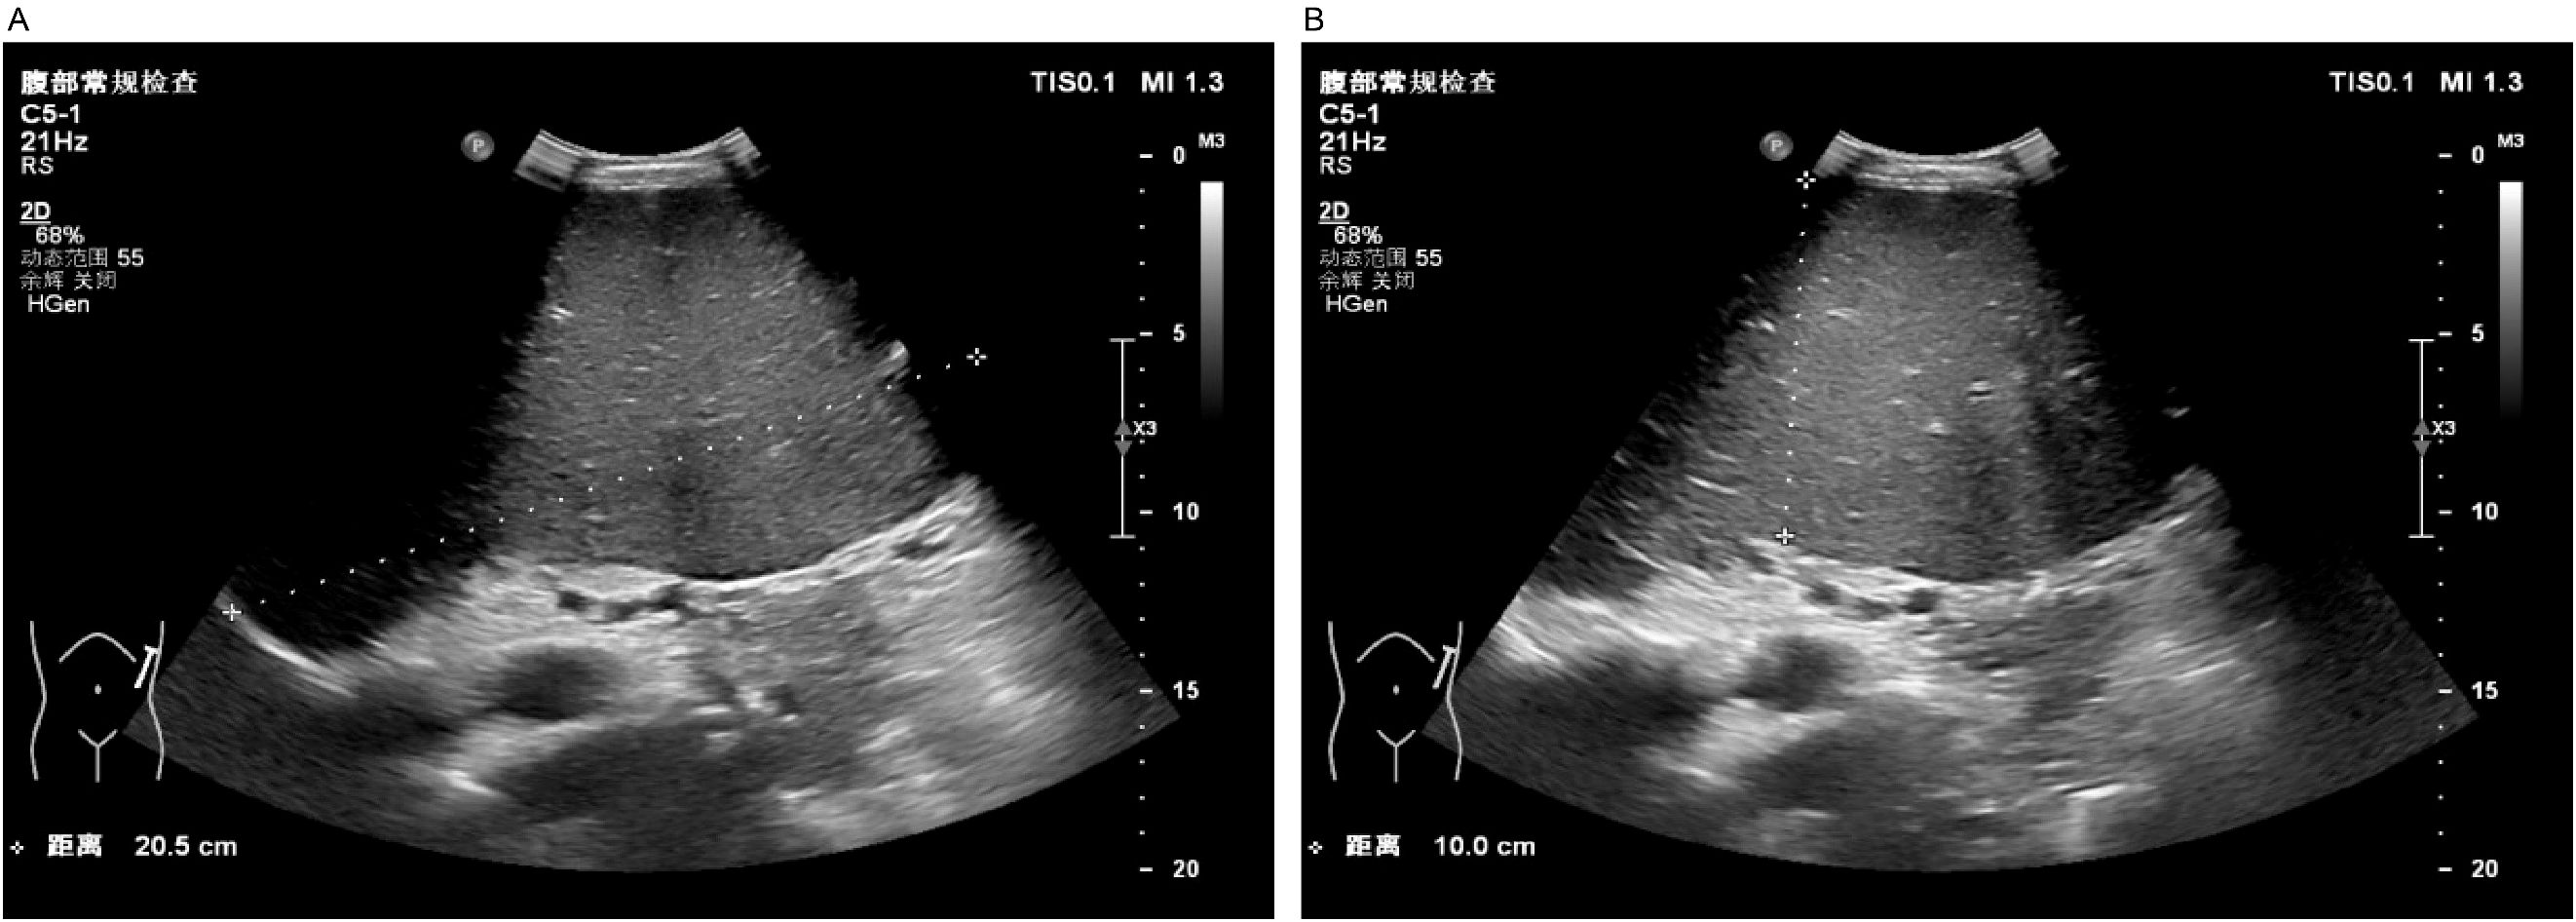

A 37-year-old male patient with a history of hypertension and no reported family history of anemia presented with a decade-long history of recurrent abdominal distension and splenomegaly, accompanied by elevated platelet counts persisting for nine years. Abdominal ultrasonography identified severe splenomegaly, characterized by a thickness of approximately 10 cm and a longitudinal diameter of approximately 20 cm, with the lower edge extending below the umbilical level and the medial border reaching the anterior midline. A patchy hypoechoic region was noted at the lower pole of the spleen, the etiology of which remains indeterminate but is most likely suggestive of an infarction (Figure 1).

Figure 1. Abdominal ultrasound. Severe splenomegaly (approximately 10 cm in thickness, approximately 20 cm in the upper pole diameter, with the lower margin extending below the umbilical level and the medial border reaching the anterior midline). Panel (A) shows the craniocaudal diameter of the spleen, while Panel (B) illustrates the thickness of the spleen.